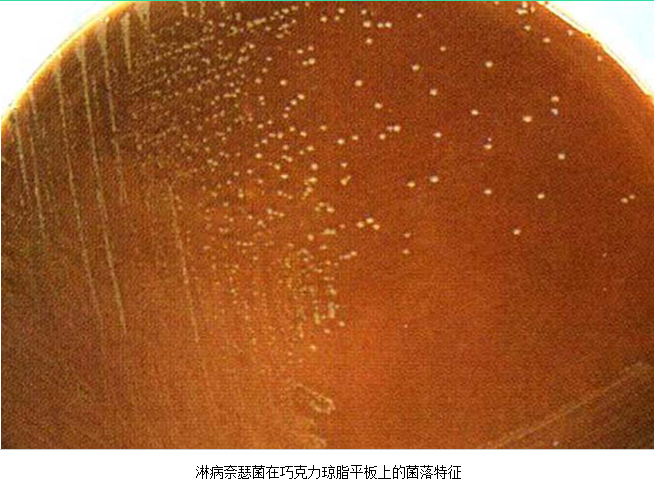

3.病原体检测 应作衣原体及淋病奈瑟菌的检测,以及有无细菌性阴道病及滴虫阴道炎。检测淋病奈瑟菌常用的方法有:①分泌物涂片革兰染色,查找中性粒细胞内有无革兰阴性双球菌,由于子宫颈分泌物的敏感性、特异性差,不推荐用于女性淋病的诊断方法。②淋病奈瑟菌培养,为诊断淋病的金标准方法。③核酸检测,包括核酸杂交及核酸扩增,尤其核酸扩增方法诊断淋病奈瑟菌感染的敏感性及特异性高。检测沙眼衣原体常用的方法有:①衣原体培养,因其方法复杂,临床少用。②酶联免疫吸附试验检测沙眼衣原体抗原,为临床常用的方法。③核酸检测,包括核酸杂交及核酸扩增,尤以后者为检测衣原体感染敏感、特异的方法。但应做好质量控制,避免污染。